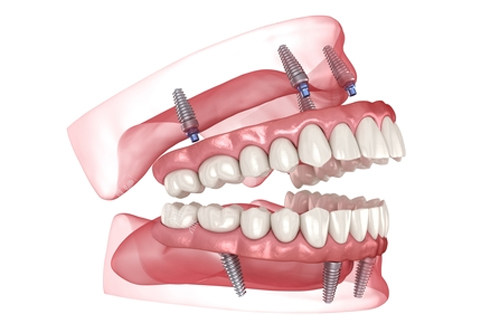

全口种植

all-on-4全口种植牙模型图